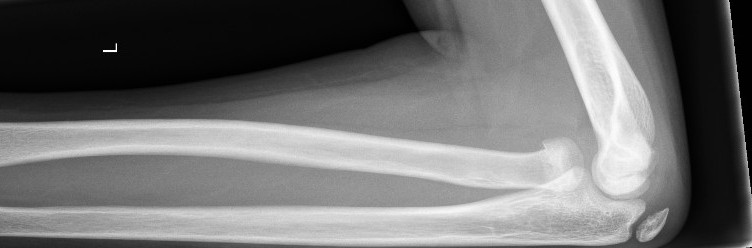

Undisplaced supracondylar fracture (Gartland type 1)1

- Collar and cuff with 90 degrees flexion.

- Orthopaedic Fracture clinic follow up in 7-10 days.

Non-displaced supracondylar fracture